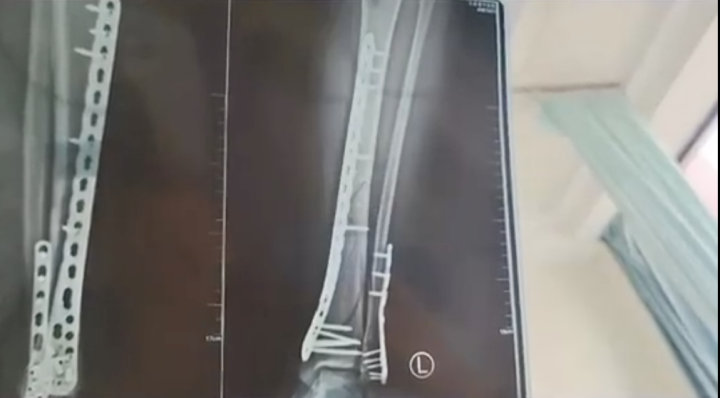

近日,话题词#女子穿7cm厚洞洞鞋崴脚粉碎性骨折#冲上了热搜第一的位置。

武女士说,自己目前已做完手术在家休养,她也提醒大家,穿增高鞋要注意。